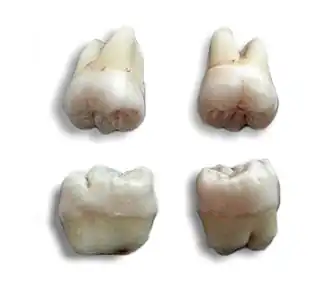

The morphology of wisdom teeth can be variable.

Maxillary (upper) third molars commonly have a triangular crown with a deep central fossa from which multiple irregular fissures originate. Their roots are commonly fused together and can be irregular in shape.

Mandibular (lower) third molars are the smallest molar teeth in the permanent dentition. The crown usually takes on a rounded rectangular shape that features four or five cusps with an irregular fissure pattern. Roots are greatly reduced in size and can be fused together.[13]